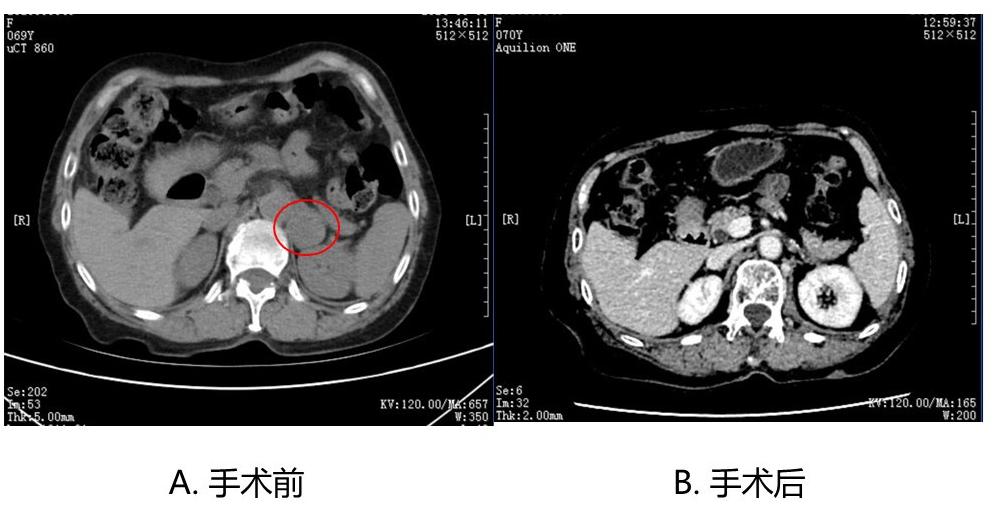

近期,一位69岁女性患者因高血压、左侧肾上腺发现3cm大小的肿物就诊于上海市公共卫生临床中心内分泌科门诊。该患者消瘦,轻度营养不良,完善实验室检查提示血多巴胺、去甲肾上腺素和肾上腺素水平明显升高,临床考虑嗜铬细胞瘤,并完善PETCT检查多发病灶的可能。

根据患者实际情况,内分泌科主任赵晓龙依据之前建立的大门诊小病房术前准备的规范流程,给予患者口服α受体阻滞剂多沙唑嗪和美托洛尔降压控制心率,同时让患者高盐饮食扩充血容量,并且指导患者如何正确测量记录血压数据,有相应的医生与护士定期电话沟通,随时了解患者服药、血压、心率等情况,并结合每周复诊调整药物剂量,使患者血压维持在120/70mmhg,心率70次/分,达到手术指征。经内分泌科、泌尿外科、麻醉科、影像科专家多学科讨论后,为该患者顺利实施手术。

术中未出现明显的血压波动,病理结果符合嗜铬细胞瘤。术后患者血压完全正常(无需服用降压药),血儿茶酚胺也恢复正常水平。嗜铬细胞瘤是罕见疑难复杂疾病,术前准备要求高,公卫内分泌科借助国外成熟的大门诊小病房模式完成术前准备,节约患者住院时间,同时依赖多学科会诊模式进行临床诊疗的充分协作,充分保证患者的医疗安全和诊疗效果。科普小贴士